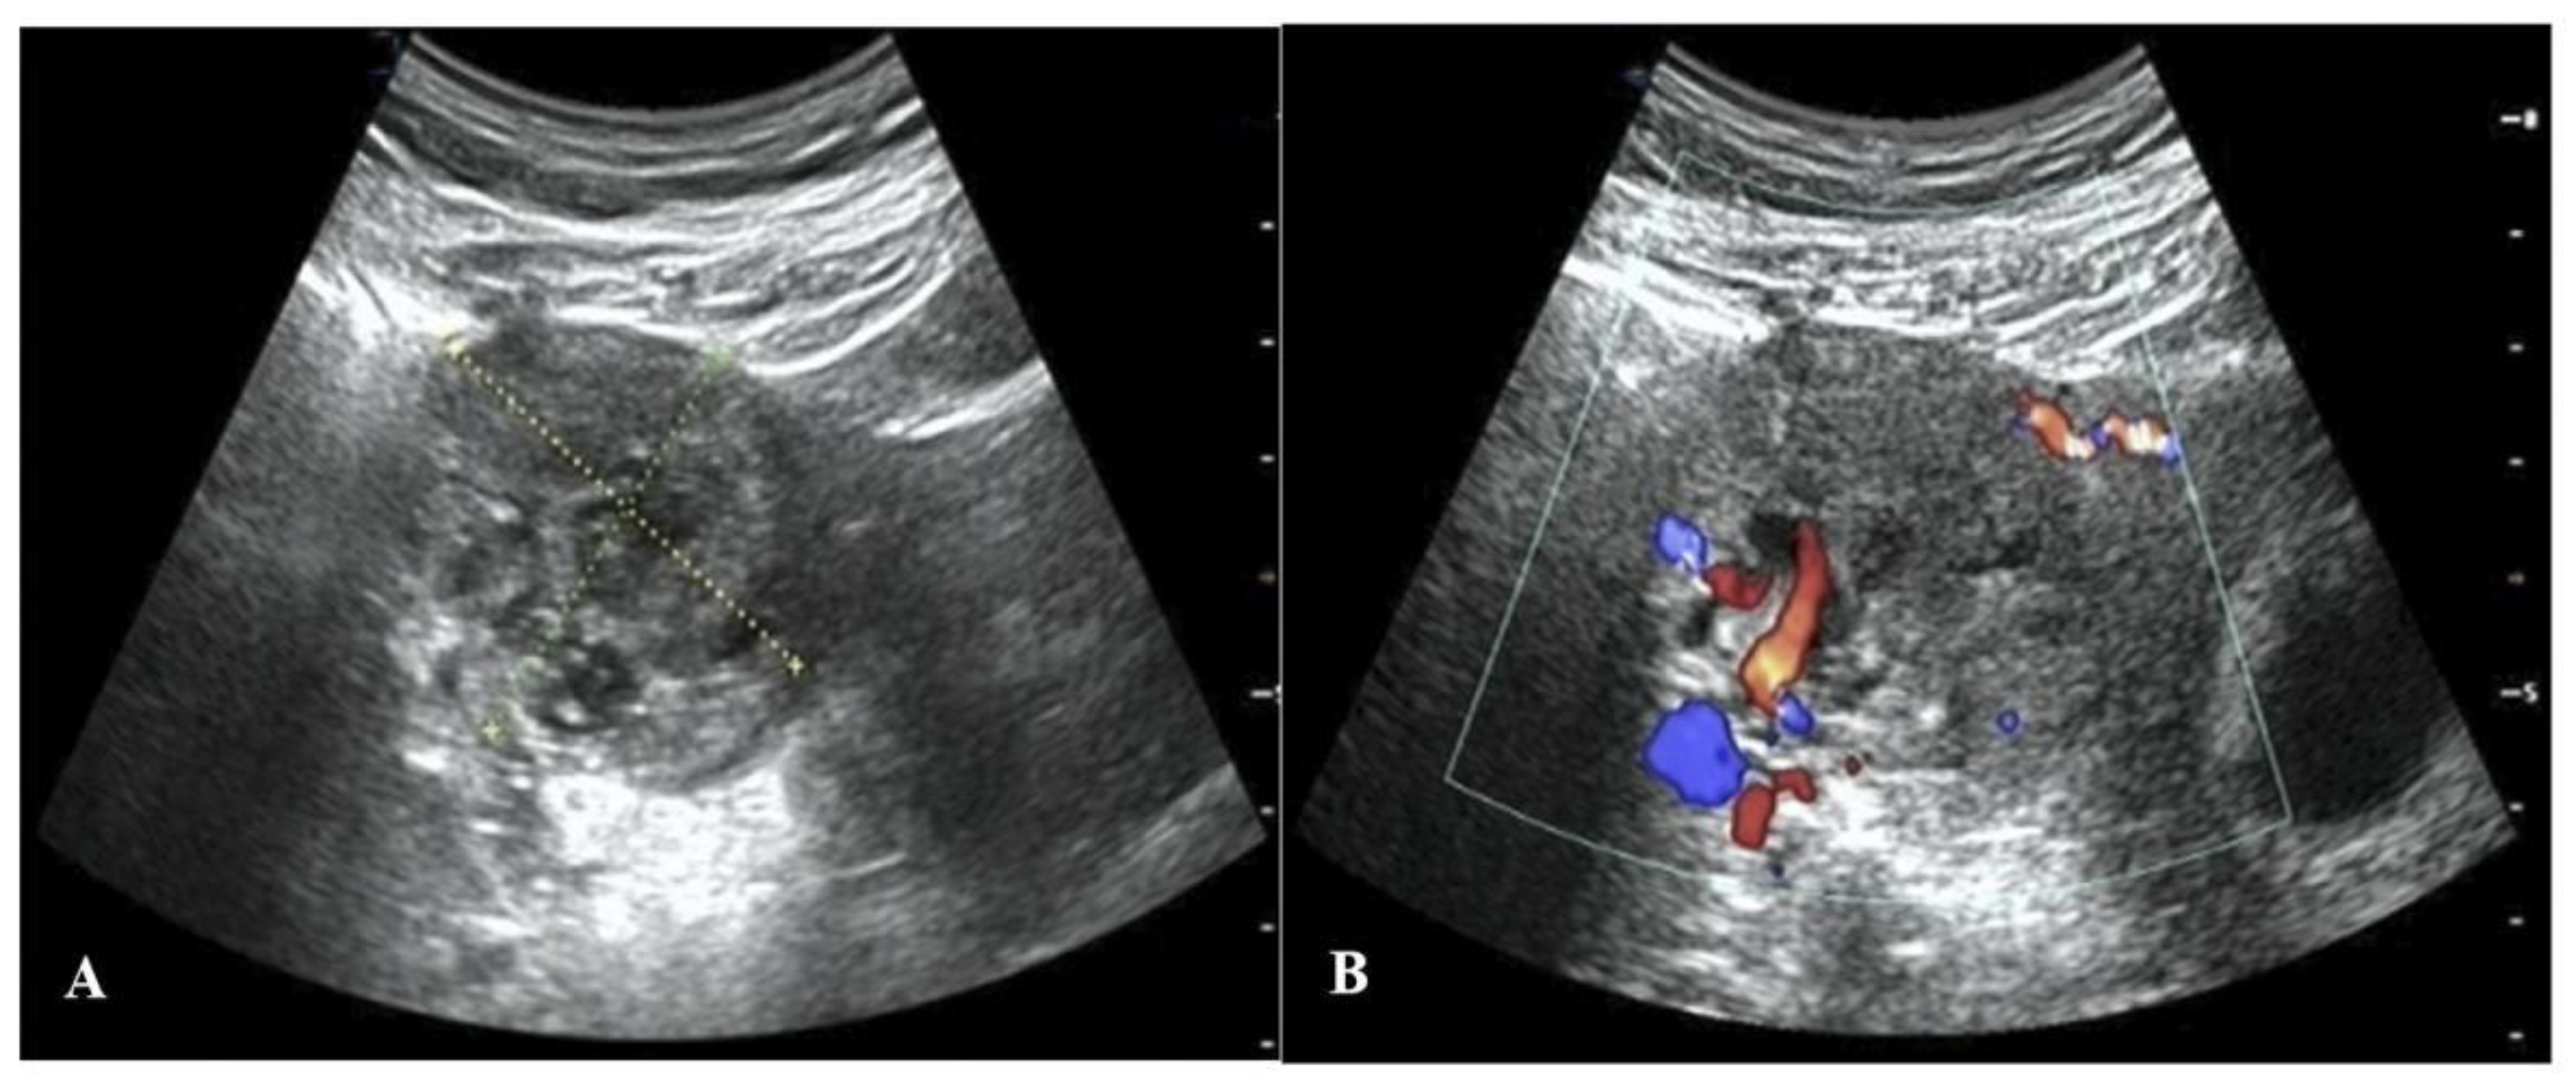

A 31-year-old woman came to Peking University Shenzhen Hospital complaining of slight vaginal bleeding and tenesmus for 8 h. She had undergone in vitro fertilization (IVF) and transferred two frozen embryos into the uterine cavity at the hospital 38 days prior. On the 14th day after embryo transfer (ET), she routinely received a serum β-human chorionic gonadotropin (β-hCG) test, which showed 2372 IU/L, indicating pregnancy. On day 30 after ET, the patient had her first ultrasound, which revealed an embryo in the uterus. During this period, the patient and the embryo were in a stable condition. However, on the 38th day after ET, she had a small amount of vaginal bleeding and tenesmus, so she returned to the hospital for treatment. Two gestational sacs were unexpectedly discovered by transvaginal ultrasonography (TVUS) on day 38 after ET: one was in the uterine cavity with a fetal bud of 15 mm long and with a fetal heartbeat, and the other was located in the right interstitial part of the fallopian tube, which was not communicated with the uterine cavity. In this gestational sac mass, there was a fetal bud about 5 mm long, and the fetal heart rate was not yet obvious, but the blood flow signal around the mass was abundant (Figure 1). In addition, the patient’s serum β-hCG level was shown to be higher than 264,000 IU/L. She was finally diagnosed with HIP based on TVUS, serum β-hCG levels, and multidisciplinary expert consultation.

Figure 1.

Ultrasound images on the 38th day after ET. (A) A two-dimensional ultrasound image: (a) the interstitial gestational sac in the interstitium of the right fallopian tube and (b) the intrauterine gestational sac. (B) A color Doppler ultrasound image showing an abundant blood flow signal around the IP.